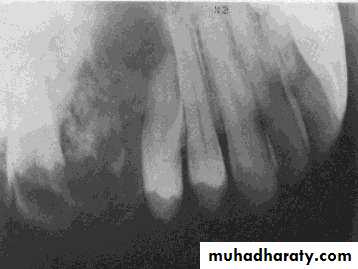

• Squamous odontogenic tumor

• Appear as non-specific radiolucent lesions. They may be well-circumscribed or ill- defined. They often appear triangular in shape and lateral• to the tooth root.

• Some time mimic sever bone loss from periodontitis.